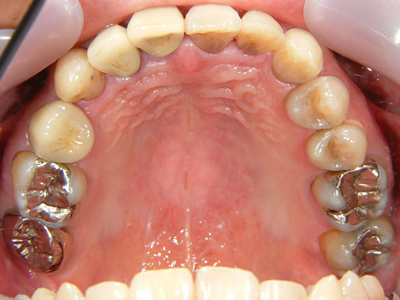

2. 初診時上顎面観

3. 初診時上顎

上顎面観では正面観よりも八重歯が顕著です。この部位2,3,4番はPCR良好な方でもまともには清掃できません。この八重歯でよく口唇に咬傷を作るうえ、ご自身でも上手く磨けずせっかくセラミックを入れたのに臭いがすると訴えておられます。4番にはパーシャルバイクのセラミック冠(自費診療と思われる)が入っています。結果論ですがこの4番の崩壊が一番顕著で抜歯となってしまいました。患者様には「高額の費用だったのに一番先にダメになった」と医療不信を持たれる原因となりました。